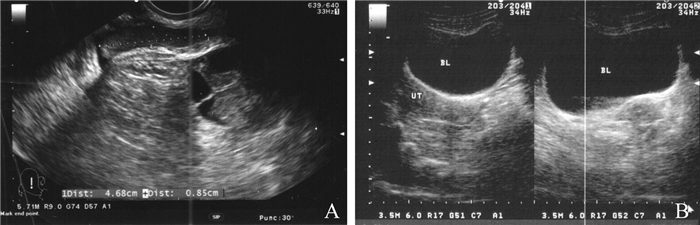

病例2 患者女,29岁。因经阴道穿刺取卵术后2 h排尿后仍有尿意、尿色较深,伴有下腹酸胀感于2017年5月15日在我院就诊。2012年患者因右侧输卵管妊娠行腹腔镜下右侧输卵管切开取胚术,2015年因左侧输卵管妊娠行腹腔镜下左侧输卵管切除术。2016年底在外院行第一周期长方案IVF,获卵9枚,体外受精后形成胚胎4枚,两次胚胎移植后未孕。2017年3月6日因继发性不孕1年来我院就诊。2017年5月15日行第二周期长方案IVF,取卵术中见右侧卵巢位于膀胱边缘,穿刺针经过部分膀胱边缘取卵,术程顺利,阴道穿刺点无活动性出血。术后2 h患者诉排尿后仍有尿意、尿色较深,伴有下腹酸胀感。患者情绪紧张,冒冷汗,予低流量吸氧。体格检查:体温36.8 ℃,脉搏97次/分,血压115/82 mm Hg,呼吸20次/分。急查血常规示:血红蛋白115 g/L,红细胞4.2×1012/L,白细胞11.5×109/L,血小板187×109/L,中性粒细胞0.79,红细胞比积0.372。B超提示:膀胱较充盈,内可见不均质混合回声包块,大小约47 mm×8 mm,内见不规则光带(图 1A)。考虑为急性膀胱损伤后的血凝块,伴尿潴留。告知患者相关病情,并建议患者入院观察和治疗。入院后,进行积极的心理支持和辅导,予留置22F三腔气囊导尿管,B超监测下使用预先加温至37 ℃的生理盐水进行膀胱冲洗。抽吸液中可见少量鲜红色血块。B超显示膀胱内混合回声团明显缩小(图 1B),抽吸液渐清亮,继续留置导尿管24 h,可见尿色清。复查血常规示:血红蛋白113 g/L,白细胞9.4×109/L,红细胞4.3×1012/L,中性粒细胞0.73,血小板157×109/L,红细胞比积0.377。凝血酶原时间11.3 s,纤维蛋白原3.03 g/L,活化部分凝血活酶时间31.5 s,凝血酶时间17.9 s。住院3 d后复查B超,结果示膀胱内未见明显异常,患者无特殊不适出院。取卵术后3 d行胚胎移植。移植术后2周查血人绒毛膜促性腺激素328 U/L,孕36周胎膜早破后顺产一活女婴。

图 1 经阴道穿刺取卵术后并发膀胱损伤患者(病例2)的B超检查结果 A:治疗前可见膀胱有不均质混合回声包块,内有不规则光带;B:治疗后混合回声团明显缩小 |